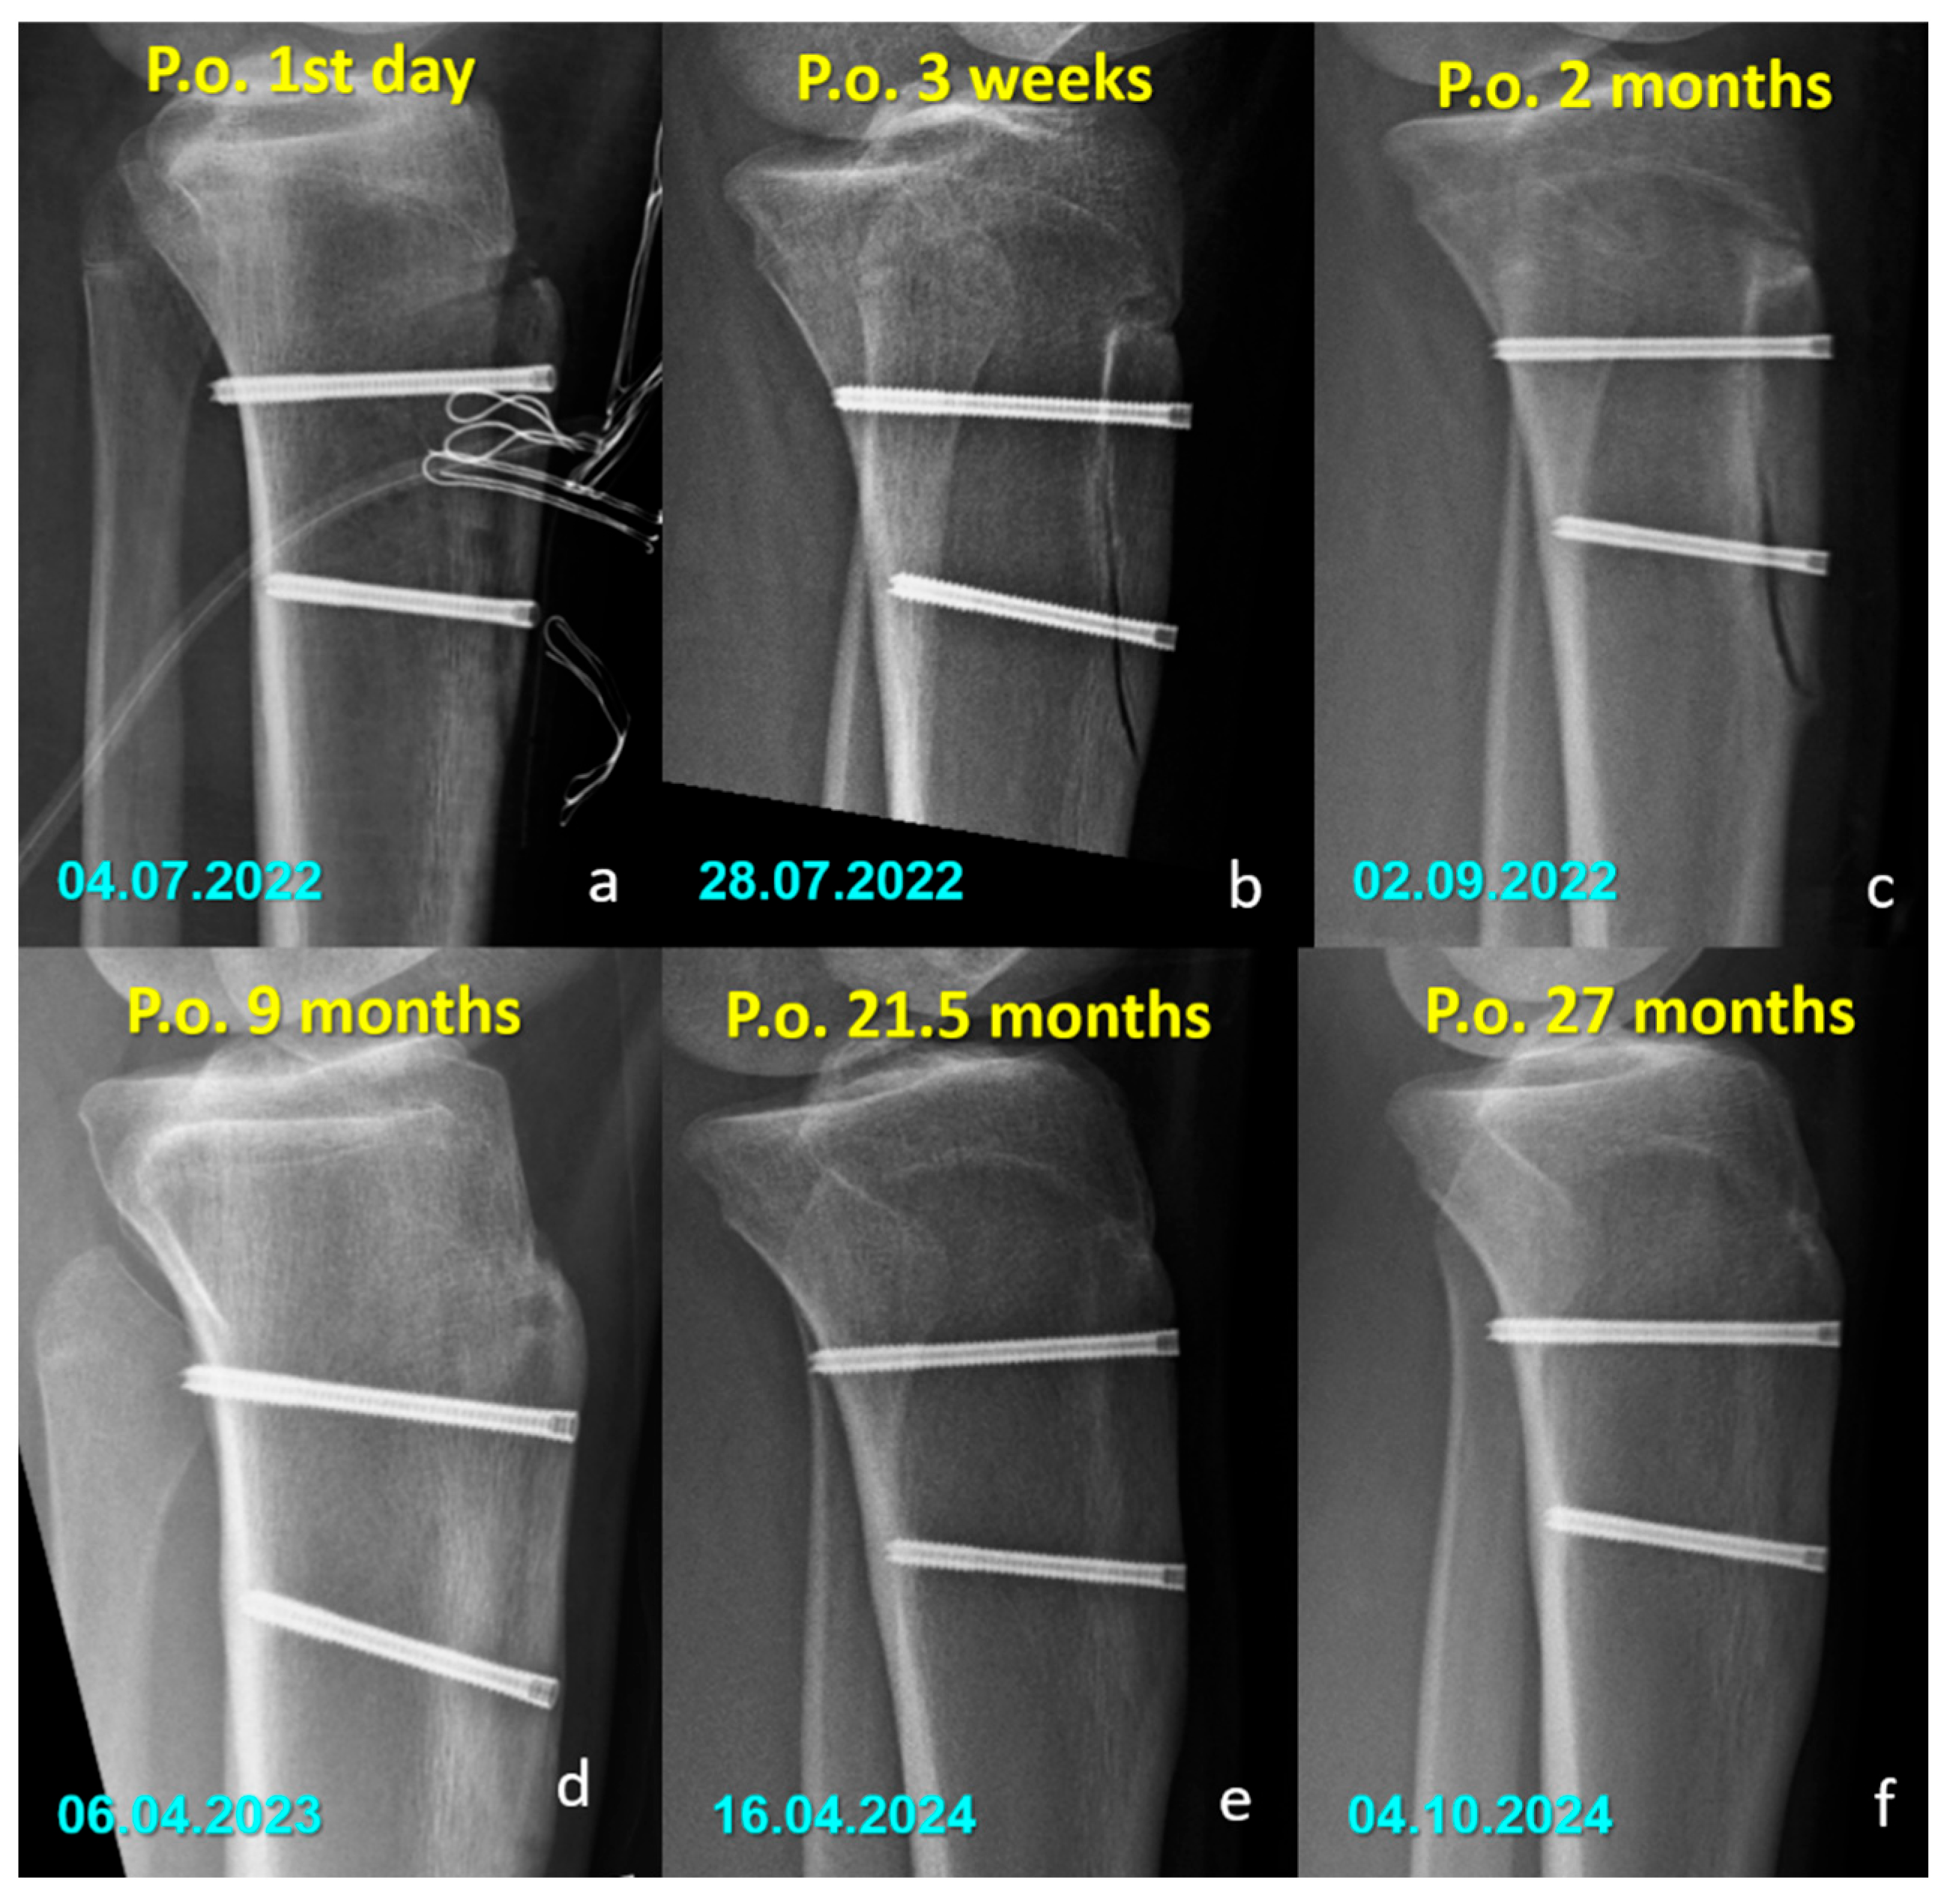

Radiographic Findings in the Mg Screw Group